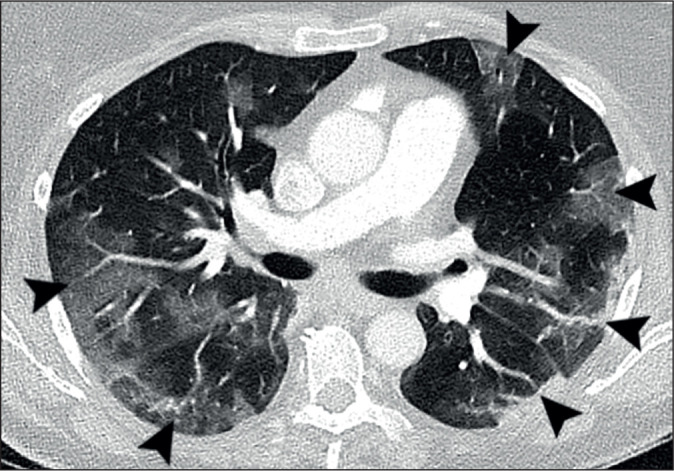

Results: Parenchymal lung damage was found in all subjects. However, airways inflammation was present in only 23% (9) and limited to small areas. Notably, vascular abnormalities were dominant and characterised by dilated peripheral pulmonary vessels supplying areas of lung damage in a gravity-dependent distribution bilaterally in 95% (38), basally in 90% (36), peripherally in 92.5% (37), and posteriorly in 90% (36). Macrothrombosis was demonstrated in 23% (7) of CTPAs. Wedge-shaped peripheral lung damage, resembling areas of pulmonary vascular congestion, were distinct in 53% (21) with or without visible macrothrombosis. Pleural effusions were seen in 28% (11). Notably, lung opacification distribution in 98% of the plain radiographs matched distribution on CT (39).